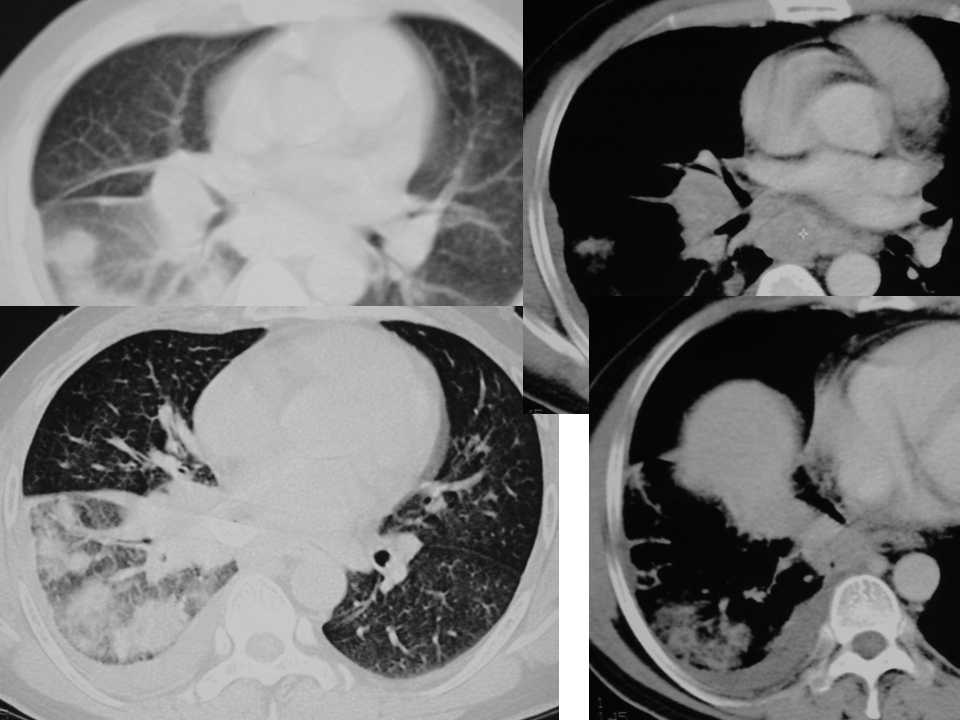

肺癌影像诊断